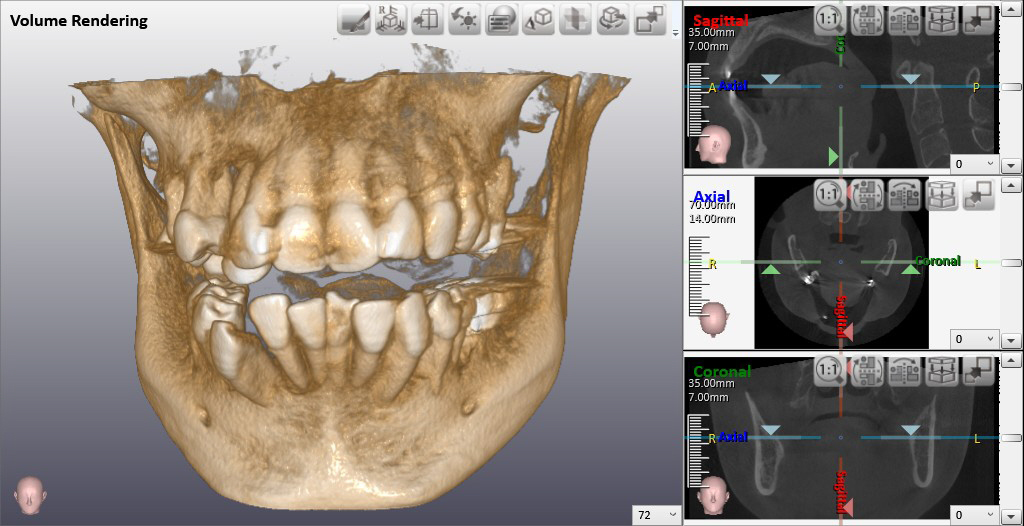

右下の親知らずに近接した下歯槽神経の位置を3次元的に把握することができます。

赤➤で囲まれた部分が下歯槽神経、黄➤下歯槽神経と親知らずがくっついていないことが確認できます。